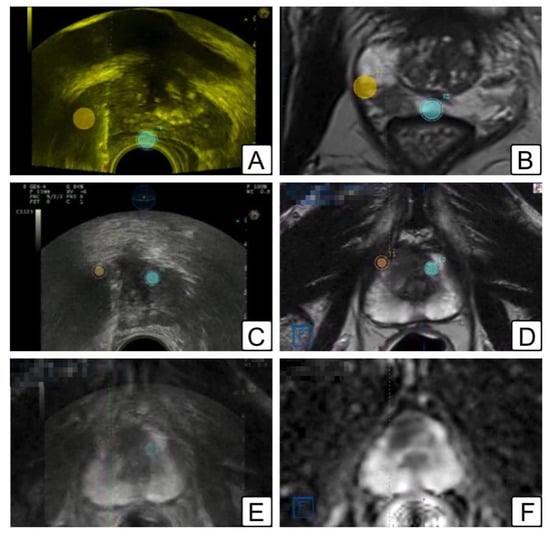

2.4. Lesion Segmentation